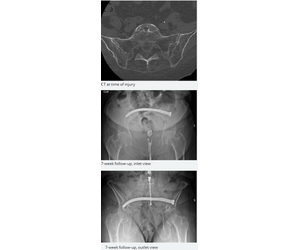

A transiliac-transsacral CurvaFix® IM Implant was placed in an outpatient procedure. At completion, the implant was appropriately positioned with a good curve. The implant was well contained within the sacrum, and well between the L5-S1 endplate.

At 7 weeks, there was no change in the position or curve of the implant, and no signs of loosening or lucency